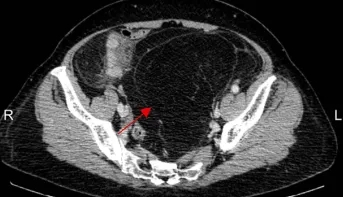

70岁、76岁、82岁,河北医大二院成功实施三例高难度腹膜后巨大肿瘤切除术

箭头示为患者二的腹膜后肿瘤

箭头示为患者三的腹膜后肿瘤 延伸至盆腔